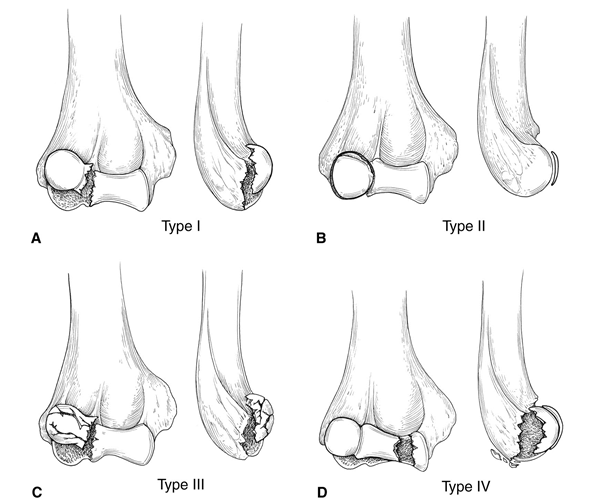

<br />Только перелом головки (головчатого возвышения, capitulum) плечевой кости 1 типа.<br /><br />Hahn лечил 63 летнюю женщину с травмой локтевого сустава 3-х летней давности и впервые в мировой литературе описал эту травму в 1853 году. К сожалению, результат лечения был неудовлетворительный.<br /><br />В последующие годы была предложена классификация переломов головки плечевой кости, в которой было выделено 4 типа:<br /><br />1 тип (Hahn-Steinthal type) представляет собой, т. наз. "полный перелом", при котором головка типично смещается кпереди и вверх. Плоскость излома лежит во фронтальной плоскости, а костный фрагмент по сути представляет свободное тело в полости сустава.<br /><br />

<br /><br /><br />2 тип (Kocher-Lorenz type) представляет собой "декортикацию" головки, когда костный фрагмент представлен преимущественно суставным хрящем.<br /><br />

<br /><br />3 тип (Broberg и Morrey) - оскольчатый перелом головки плечевой кости.<br /><br />4 тип McKee - перелом головки плечевой кости с переходом линии излома на блок.<br /><br />